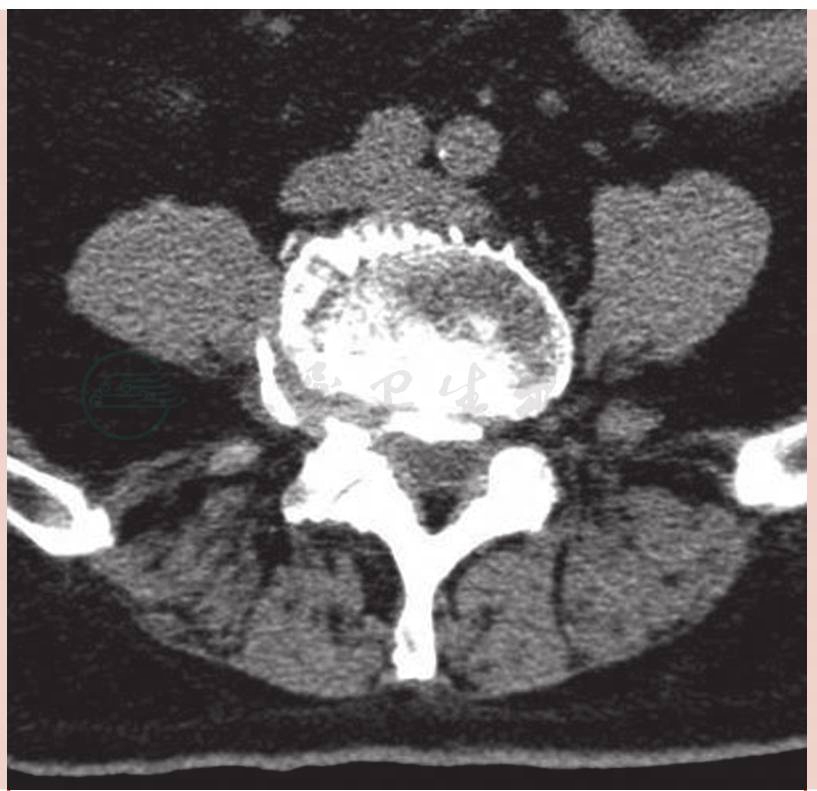

术前CT检查提示:腰椎生理曲度存在,稍侧弯。L4-S1椎间隙变窄,内可见真空征。L2-3、L3-4、L4-5、L5-S1椎间盘膨出,后缘压迫相应硬膜囊。L1-5椎体边缘可见骨质增生变尖(图2)。右侧L4-5椎间孔因骨质增生及椎间盘膨出变窄(图3)。各腰椎椎体小关节见骨质增生硬化(图4)。

图3 术前CT轴位示L4-5椎间盘向右后方突出,骨化明显